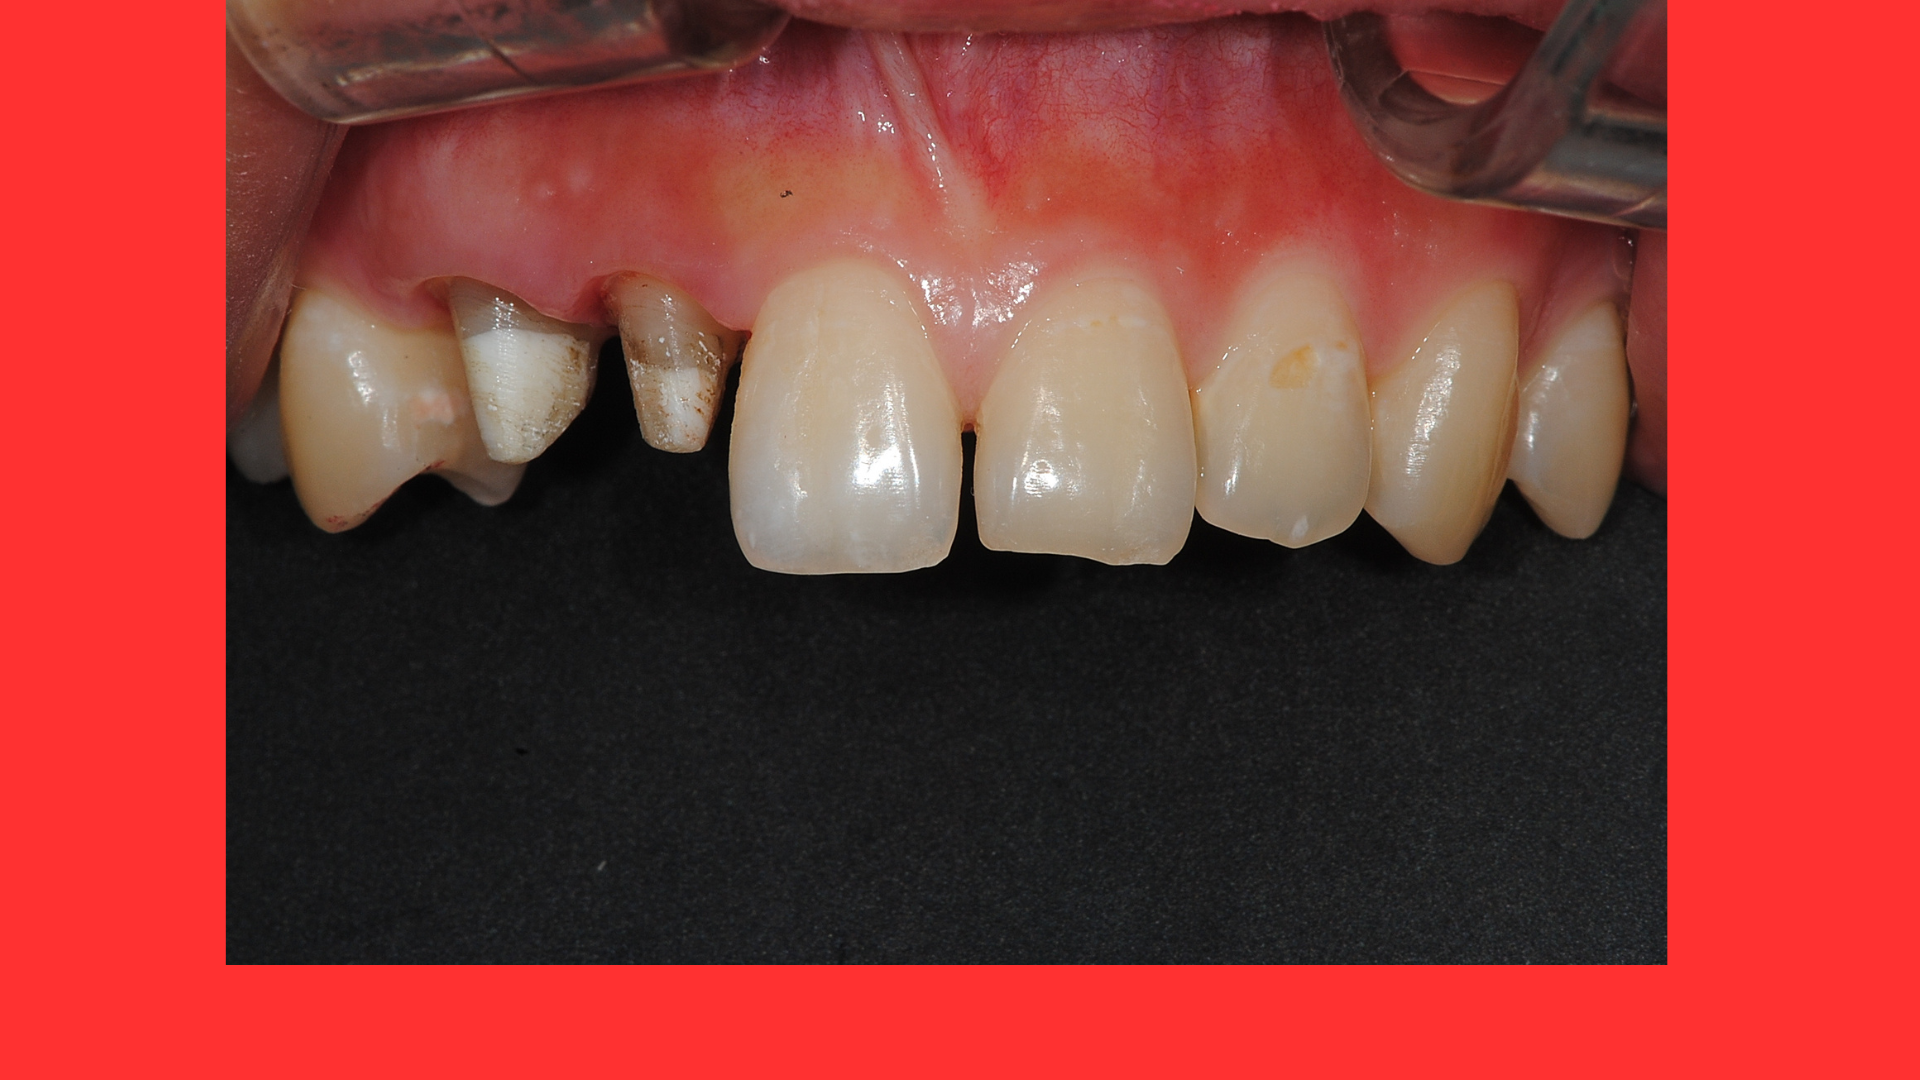

자... 흰색부분이 새로 만들어낸 치아를 대신하는 코어입니다.

그아래의 누런 색이 충치를 다 제거하고 남은 건전 치아에 해당합니다.

자... 다른 사진입니다. 잇몸몰딩이 잘 되 있음을 볼수 있습니다.